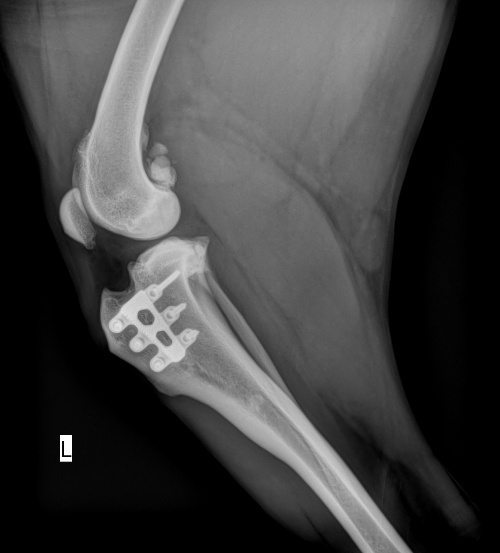

Erst mit der Zeit verwächst sich der Knochen mit dem Implantat und erlangt anschließend wieder seine vollständige Stabilität. Folgendes Bild zeigt denselben TTA RAPID® Käfig 16 Monate nach der Operation. Hier ist zu sehen, wie der Knochen dank der neuartigen 3D-Herstellung von TTA RAPID vollständig durch das Implantat hindurch wachsen konnte.

TTA RAPID® Röntgenbild 16 Monate nach der Operation →